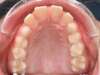

Chevauchement sévère. Traitement multibague sans extraction.

Avant

Après